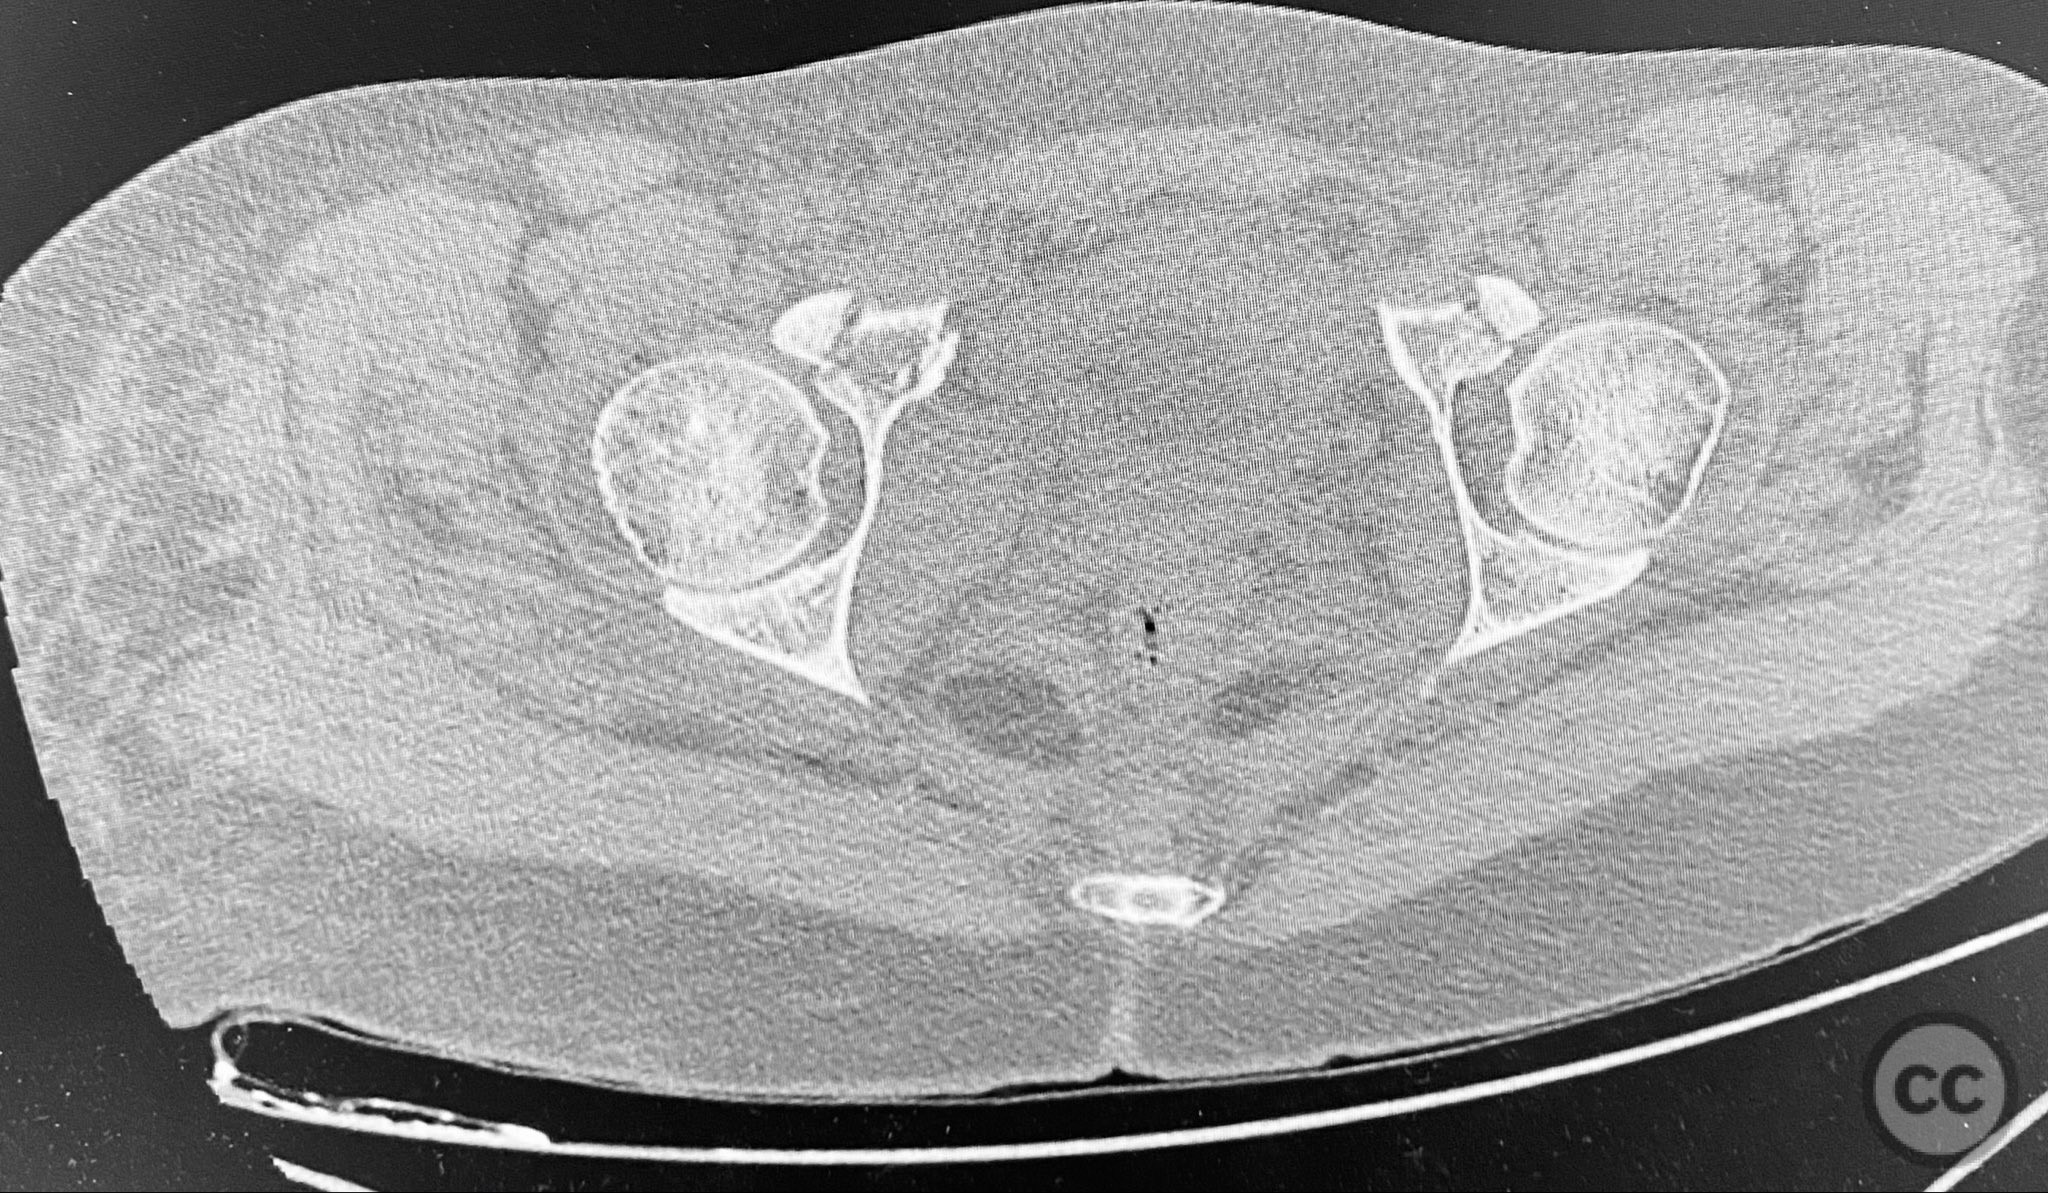

Clinical and radiological findings:  A middle-aged patient involved in a motor vehicle collision presented initially with a closed ankle fracture-dislocation and minimal pelvic complaints. Following closed reduction and splinting of the ankle, the patient developed severe pelvic pain (9/10) with any attempted movement. Neurological and vascular examination was not specified. Computed tomography demonstrated minimally displaced fractures of the posterior ilium, sacral ala, and bilateral pubic rami. AP CT surface renderings revealed subtle but clinically significant displacement and deformity of the pelvic ring, which was difficult to appreciate on standard axial images.

Anatomical surgical approach:  Percutaneous approach: Small stab incisions were made over the crista iliaca and sacral entry points as determined by preoperative imaging. Under fluoroscopic guidance, guidewires were advanced across the sacroiliac joint and sacral ala as indicated. Cannulated screws were inserted percutaneously to stabilize the unstable posterior pelvic ring and rami fractures.

Intraoperative assessment confirmed instability at the posterior pelvic ring with manual stress testing under fluoroscopy. Reduction was achieved with gentle manipulation and maintained during percutaneous screw insertion. The use of intraoperative inlet and outlet views was critical for accurate screw placement and confirmation of reduction. The minimally invasive technique minimized additional soft tissue trauma in this polytrauma patient.